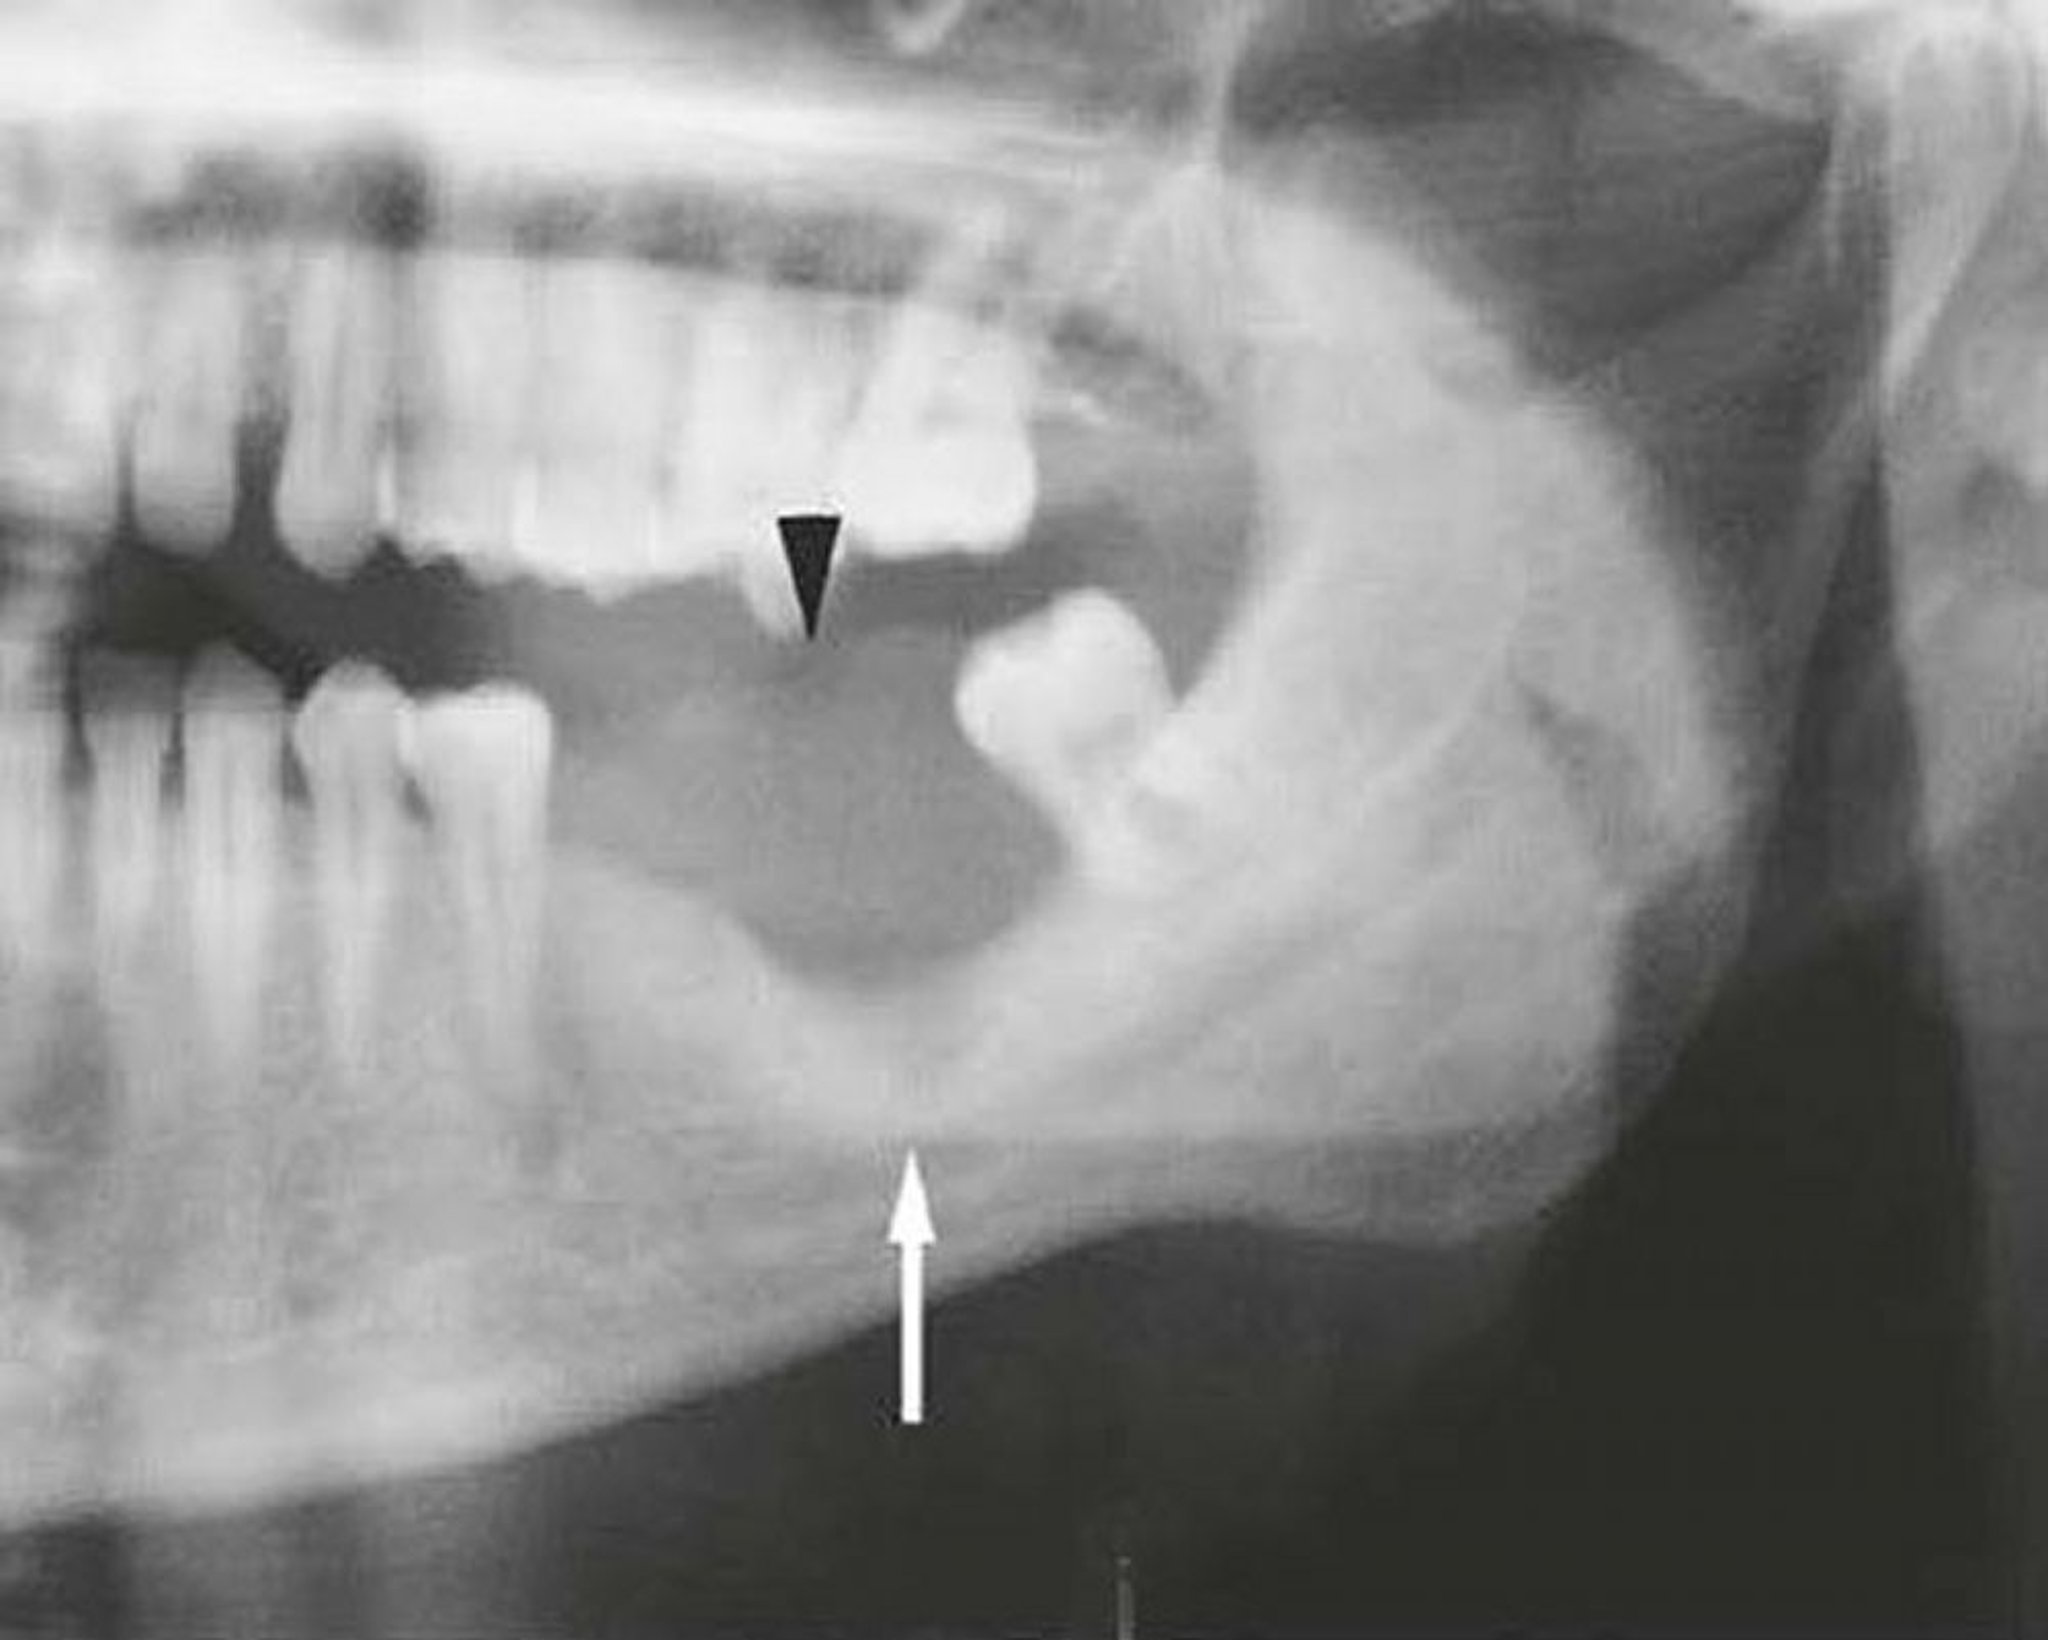

Плоскоклеточная карцинома нижней челюсти

Это изображение нижней челюсти, пораженной плоскоклеточной карциномой, показывает мягкие ткани (стрелка) и разрушение кости (стрелка).